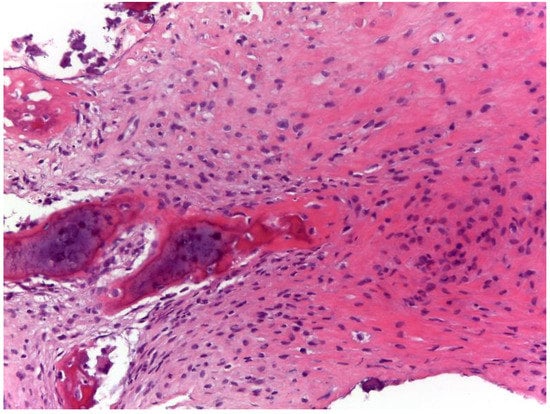

2. Detailed Case Description

2.1. Oncological Staging